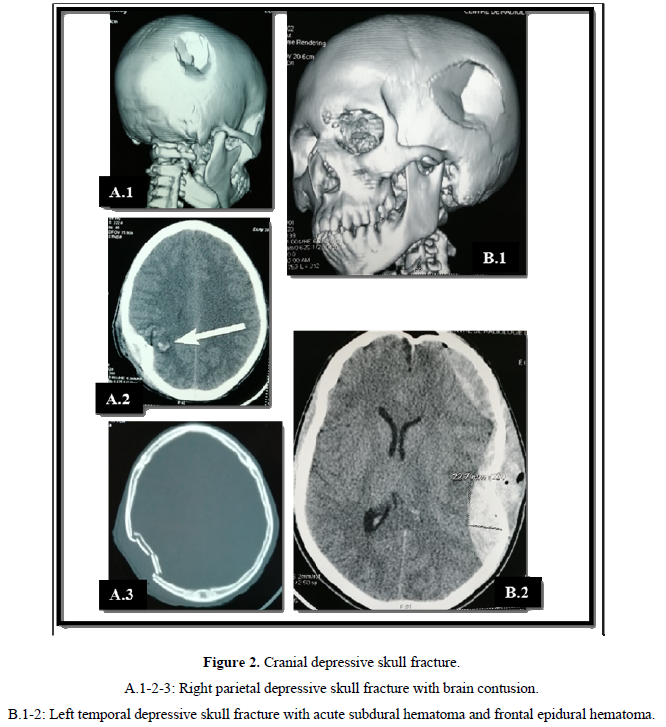

Computed tomography (CT) was the exam of choice for diagnosing lesions. It was performed in all patients and had made it possible to highlight a depressed skull fracture in 45 patients (62.5% of the cases) (Figure 2). These depressed skull fractures were isolated in 7 patients (15.6% of cases). They were associated with brain contusions in 36 cases (80%) Figure 2A and acute subdural hematoma in 2 patients (4.4%) Figure 2B. Isolated brain contusion was diagnosed in 18 patients (25%). Extradural hematoma (Figure 3C) and craniocerebral wound (Figure 3C) each accounted for 2.7% (2 cases). In 5 patients (7%), the CT scan was normal.